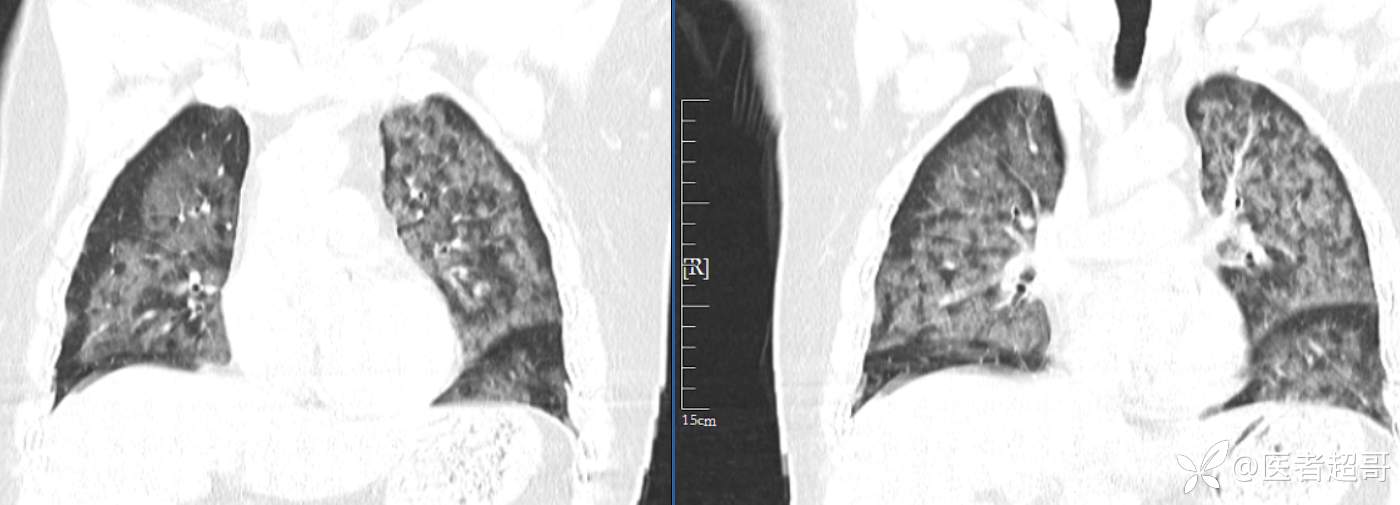

【影诊笔记574】胸痛就诊检查,发现双肺多发高密度,请赏析!

患者性别:女

患者年龄:47岁

主诉:胸痛就诊

简要病史:因“胸痛就诊”,行冠脉CTA检查,数小时后出现高热,伴畏寒寒战、气喘,暗红色泡沫样痰。

急性肺水肿 (17)